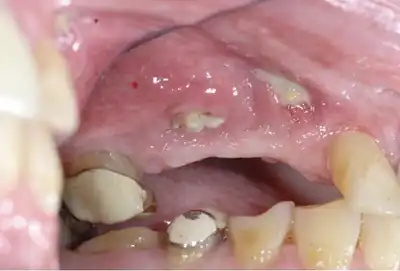

Osteonecrosis of the jaw of the upper left jaw in a patient diagnosed with chronic venous insufficiency

Osteonecrosis of the jaw affecting the upper jaw